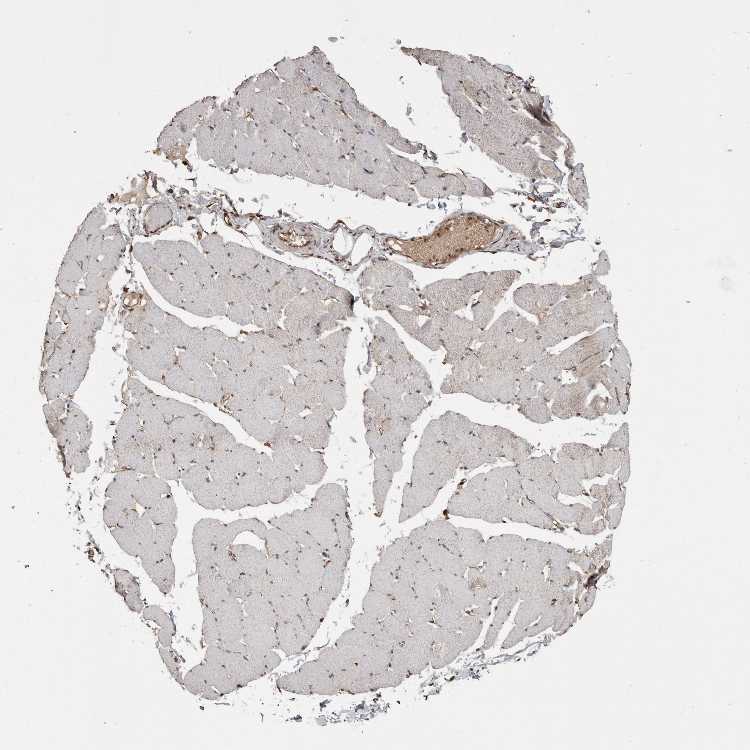

SKELETAL MUSCLE - Antibody stainingi

Antibody staining in the annotated cell types in the current human tissue is reported as not detected, low, medium, or high, based on conventional immunohistochemistry profiling in selected tissues. This score is based on the combination of the staining intensity and fraction of stained cells.

Each image is clickable and will lead to virtual microscopy that enables deeper exploration of all samples and also displays staining intensity scores, fraction scores and subcellular localization as well as patient and tissue information for each sample.

Antibody HPA014179Antibody CAB025128

Myocytes LowNot detected